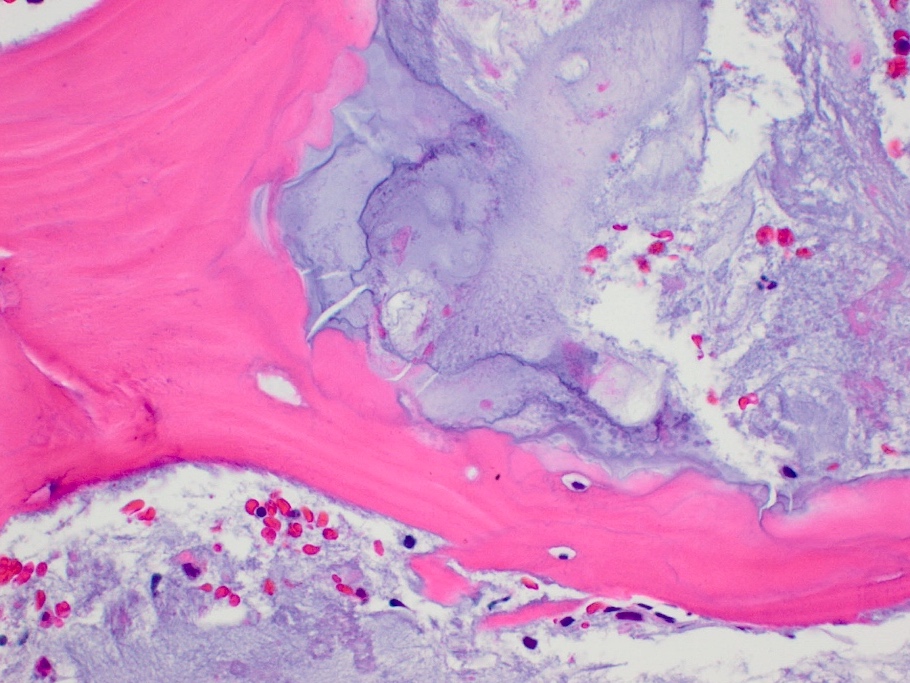

Microscopic (histologic) description

- Lobulated growth pattern (J Dent Res Dent Clin Dent Prospects 2011;5:98)

- Lobules have irregular shapes and sizes and may be separated by fibrous bands containing small vessels (Virchows Arch 2012;460:95)

- Lobules are composed of abundant hyaline cartilage matrix (sometimes with mucoid / myxoid changes) and permeate and entrap lamellar bone trabeculae

- Cellularity is slightly higher than in enchondroma

- Cells show moderate eosinophilic to vacuolated cytoplasm

- Nuclei are small and uniform with condensed chromatin (lymphocyte-like); sometimes they show open chromatin with visible nucleoli (Am J Surg Pathol 2009;33:50)

- Mitoses and significant nuclear pleomorphism are absent

- Binucleation can be observed

- Necrosis can be seen

- In cases arising from pre-existing enchondromas, areas of enchondroma with calcifications can be present

- In cases arising from pre-existing osteochondroma, evidence of this tumor can be seen (Mod Pathol 2012;25:1275)

Microscopic (histologic) images

- Bone, left 5th and 4th metatarsals, excision:

- Atypical cartilaginous tumor (see microscopic description)

- Microscopic description: Examination of the histopathologic sections reveals mature trabecular bone with juxtaposed cartilaginous proliferation, characterized by low to moderate cellularity, chondrocytes with occasional binucleated cells and mild atypia in a hyaline cartilage matrix. Foci of necrosis, nonischemic type are seen. Given the presence of nonischemic type necrosis, the large size of the tumor and the cellular atypia, the tumor is most consistent with atypical cartilaginous tumor that may have arisen from an osteochondroma.

Practice question #1

A 41 year old woman complained of an enlarging mass at her left proximal humerus. Xrays showed a lucent lesion with indistinct borders and endosteal scalloping. MRI showed an irregular, expansile, avidly enhancing mass. A biopsy of the lesion was performed and is shown above. What is the diagnosis?